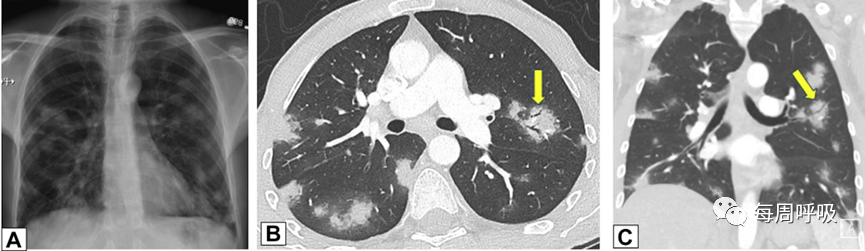

GGO(单独或呈铺路石状)是OP的另一常见胸部CT表现。同样,对于此类表现,需要进行广泛的鉴别诊断。鉴别诊断包括肺泡蛋白沉积症,感染(如耶氏肺孢子菌肺炎),结节病,外源性脂质性肺炎,粘液腺癌,以及呋喃妥因诱导的OP。就目前的相关性而言,COVID-19的典型外观与OP的外观有显著重叠(图27)。与电子烟或电子烟产品使用相关的肺损伤是另一个患病率不断上升的疾病,其结果可能与OP的结果相同(图28)

图27 COVID-19和机化性肺炎(OP)。一名55岁男性确诊COVID-19, CT表现典型。肺中部(A)和肺下段(B)的CT平扫图像显示右肺上叶磨玻璃影(GGO)伴小叶内间隔增厚,各肺下叶周边均有GGO和实变影,左肺下叶为小叶周围型。这些表现也是典型的OP。

图28 电子烟或电子烟产品使用相关的肺损伤(EVALI)和机化性肺炎(OP)。一名有电子烟吸烟史的36岁男性出现重度呼吸急促和低氧血症。薄层CT平扫显示双侧大面积实变和磨玻璃影,双侧小叶间隔增厚。外科肺活检结果显示弥漫性肺泡损伤,考虑为EVALI。这种影像学模式也可见于OP。